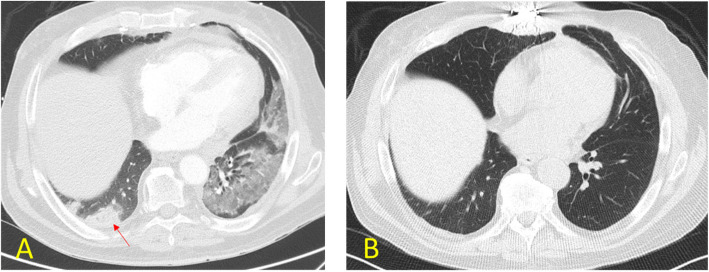

目的:急性肺栓塞(PE)是肺移植受者(LTR)面临的重大挑战,即使有预防性抗凝治疗。由于该人群并发症的风险增加,急性PE的最佳治疗方法仍不确定。本回顾性病例系列旨在阐明使用Inari装置(MT)和导管定向溶栓(CDT)经皮机械取栓治疗肺移植患者急性PE的结果。材料和方法:本研究分析了连续9例经ct血管造影(CTA)证实的肺移植后急性PE患者的治疗结果。治疗干预包括MT或CDT。随访评估包括治疗后至少1年至3年,评估各种参数,包括ICU住院时间、心室压、肺功能和实验室检查。结果:MT和CDT技术成功率均为100%,肺血流恢复顺利,血流动力学参数改善,1年生存率为100%。结论:经皮MT和CDT治疗肺移植患者急性PE是可行和有效的。这些治疗导致血栓快速溶解,治疗后改善,并提高总生存率。

Purpose: Acute pulmonary embolism (PE) presents a significant challenge in lung transplant recipients (LTR), even with prophylactic anticoagulation. Due to the heightened risk of complications in this population, the optimal treatment approach for acute PE remains uncertain. This retrospective case series aims to elucidate the outcomes of percutaneous mechanical thrombectomy with the Inari device (MT) and catheter-directed thrombolysis (CDT) in managing acute PE in lung transplant patients.

Materials and methods: This study examines the treatment outcomes of nine consecutive post-lung transplantation patients with acute PE confirmed with Computed Tomography Angiography (CTA). Treatment interventions included either MT or CDT. Follow-up assessments encompassed a minimum of one year and up to 3 years post-treatment, evaluating various parameters including ICU stay, ventricular pressures, pulmonary function, and laboratory tests.

Results: Both MT and CDT achieved a 100% technical success rate, leading to the successful restoration of pulmonary blood flow and improvements in hemodynamic parameters, with a one-year survival rate of 100%.

Conclusion: Percutaneous treatments, including MT and CDT, demonstrate feasibility and efficacy in managing acute PE among lung transplant patients. These treatments lead to rapid thrombus resolution, post-treatment improvements, and enhanced overall survival.